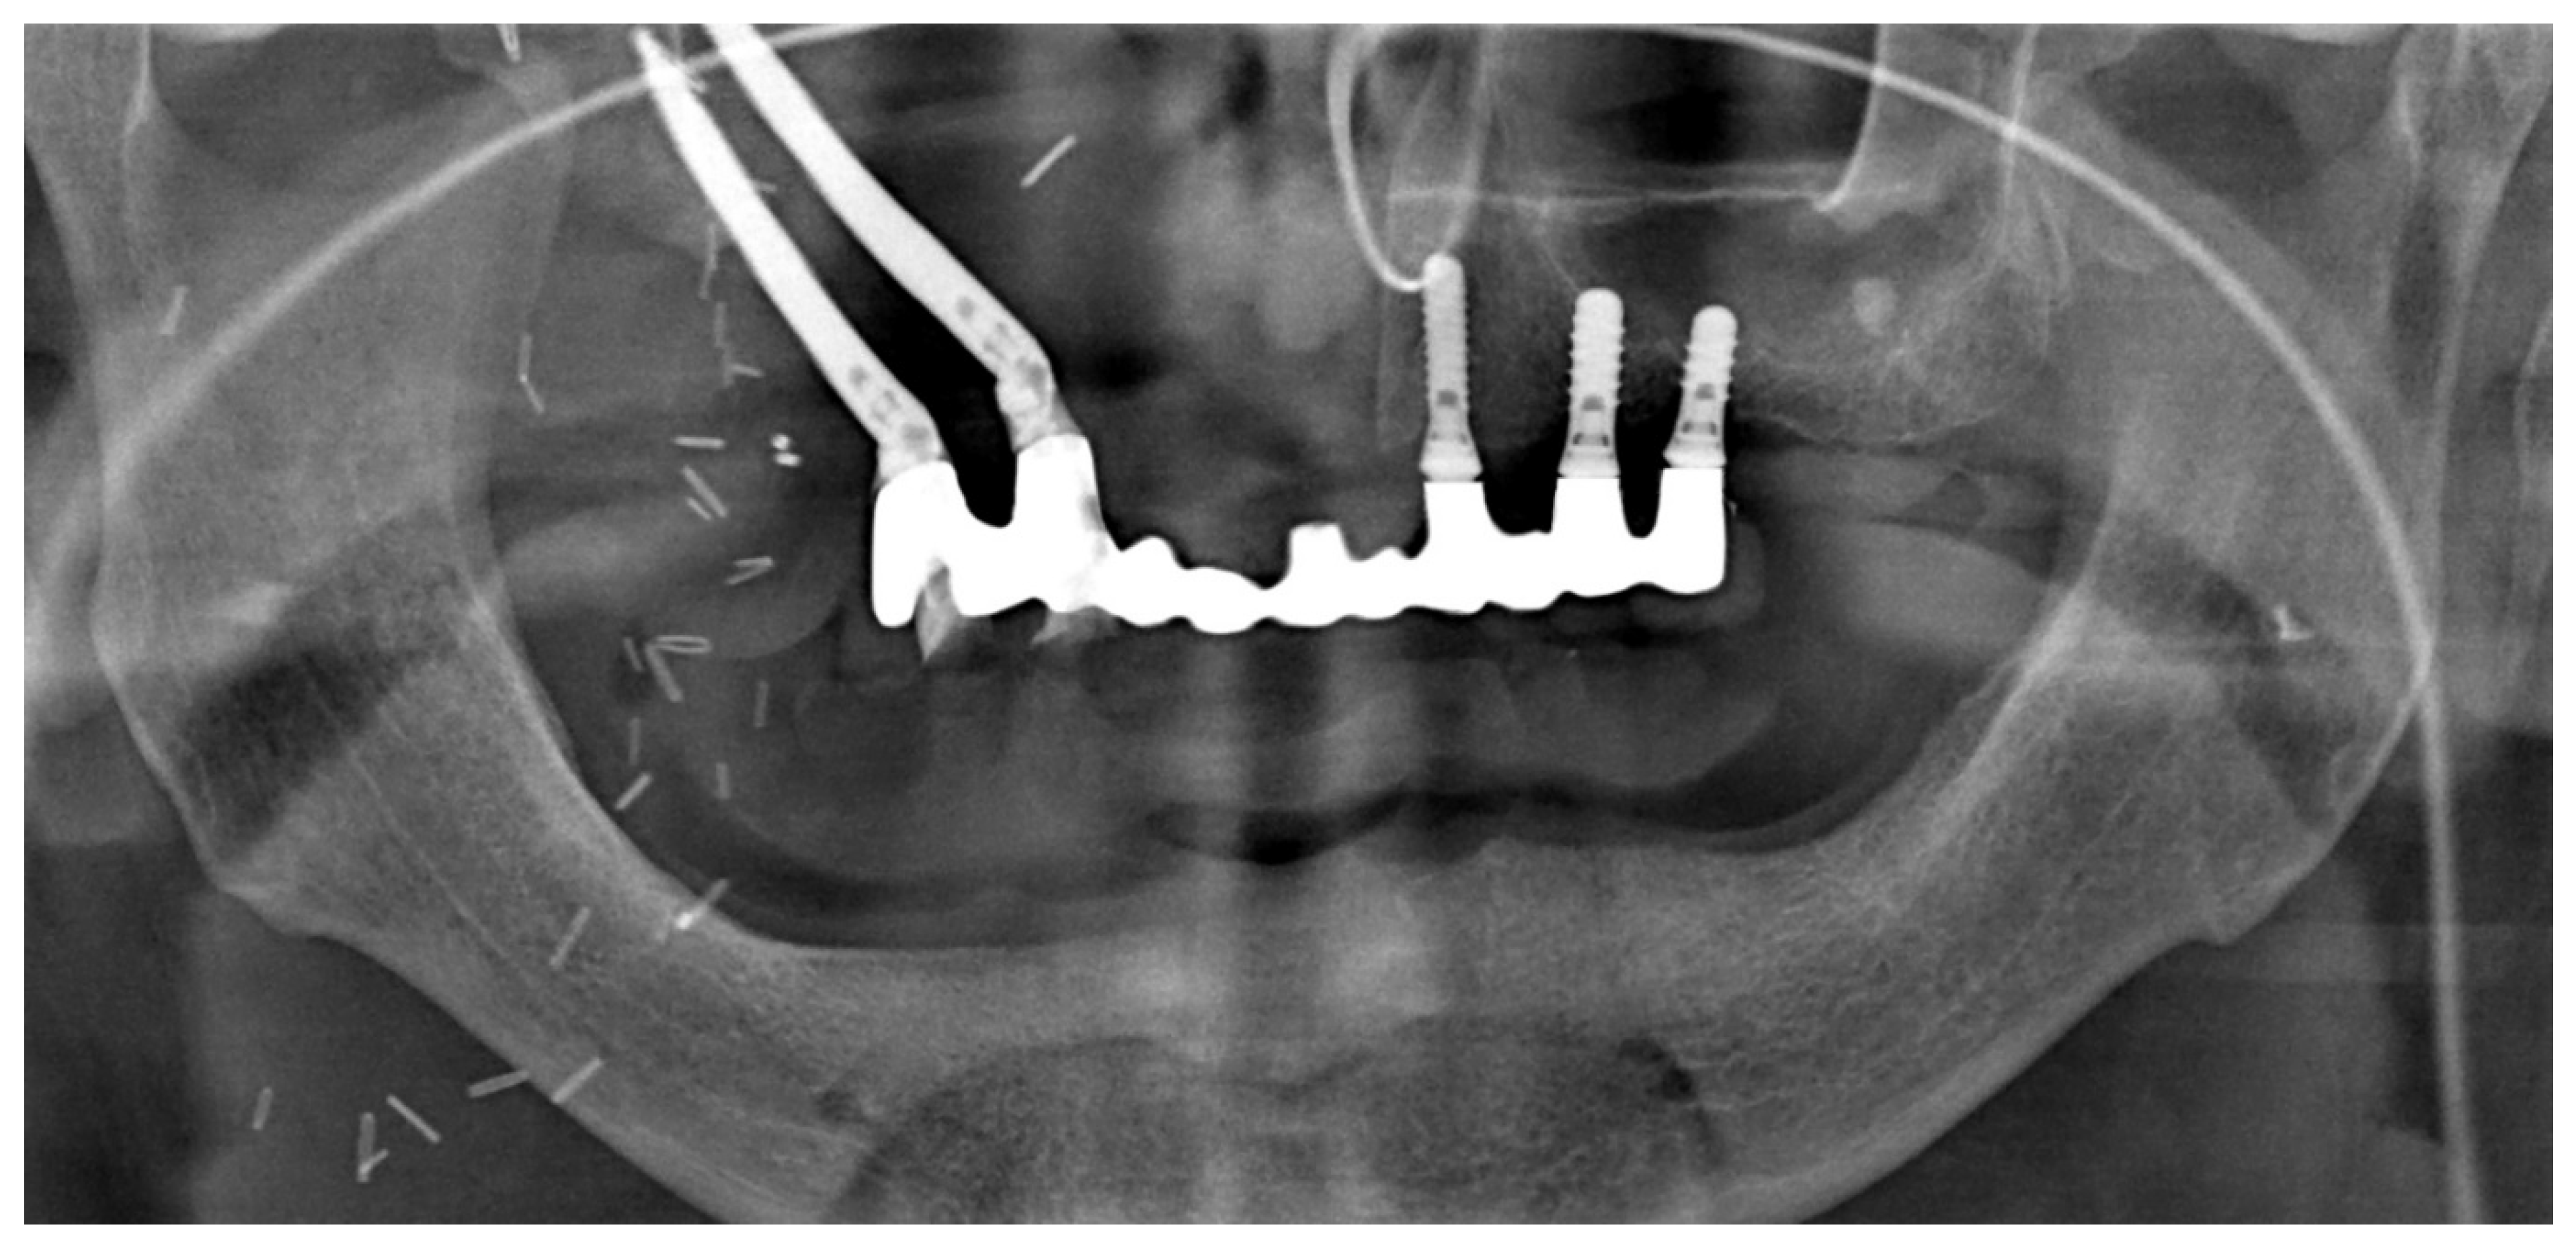

4. Surgical Technique

Post-Operative Report